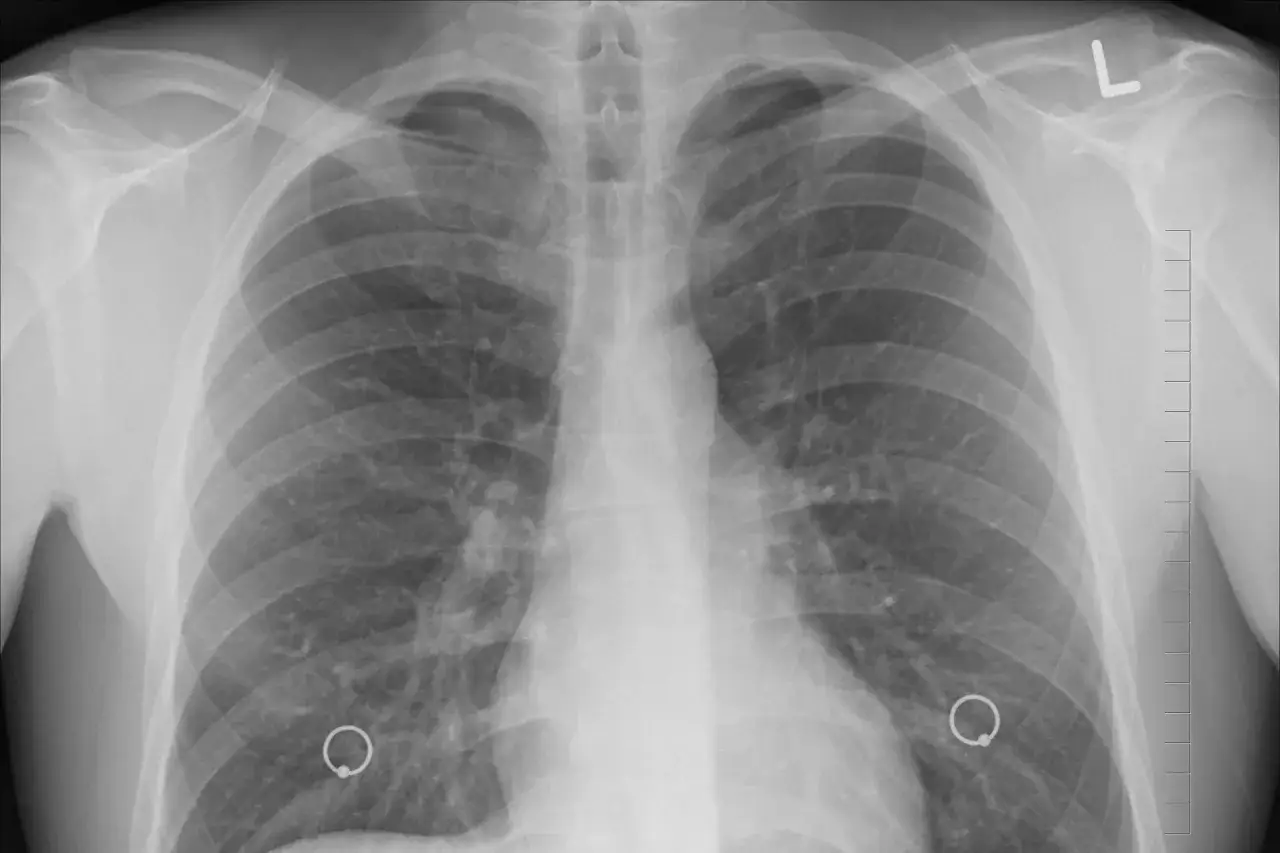

W medycynie, do oceny stopnia zaawansowania rozedmy płuc, a szerzej POChP, stosuje się międzynarodową klasyfikację GOLD (Global Initiative for Chronic Obstructive Lung Disease). Jest to standard, który pomaga lekarzom w diagnozowaniu, monitorowaniu i planowaniu leczenia. Kluczowym badaniem diagnostycznym w tej ocenie jest spirometria, która mierzy pojemność płuc i przepływ powietrza przez drogi oddechowe.

Najważniejszym wskaźnikiem spirometrycznym w kontekście rozedmy jest FEV1 (natężona objętość wydechowa pierwszosekundowa). Jest to objętość powietrza, którą pacjent jest w stanie wydmuchać z płuc w ciągu pierwszej sekundy maksymalnego wydechu. Wartość FEV1, wyrażona jako procent wartości należnej (czyli oczekiwanej dla osoby w danym wieku, płci i wzroście), mówi nam o stopniu zwężenia dróg oddechowych i uszkodzenia płuc. Im niższa wartość FEV1, tym bardziej zaawansowana jest rozedma.